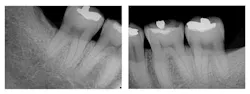

Figure 3: Three-year post-treatment radiographs

Evaluation-A six-month evaluation demonstrated reattachment (see Figure 2). The radiograph of tooth No. 18 exhibited 7.4 mm bone loss on the distal surface, reflecting an increased bone height of 4.4 mm. For tooth No. 31, the radiograph exhibited 6.2 mm bone loss, reflecting an increased bone height of 2.2 mm. Epithelial attachment gain was clinically evident as well (see Table 2). Pocket depths had marked improvement with elimination of furcation involvement on both teeth, decreased mobility of tooth No. 18, and no increase in recession. The patient also submitted three-year post-treatment radiographs taken by the dental hygienist of record (see Figure 3) with evidence of bone stability.